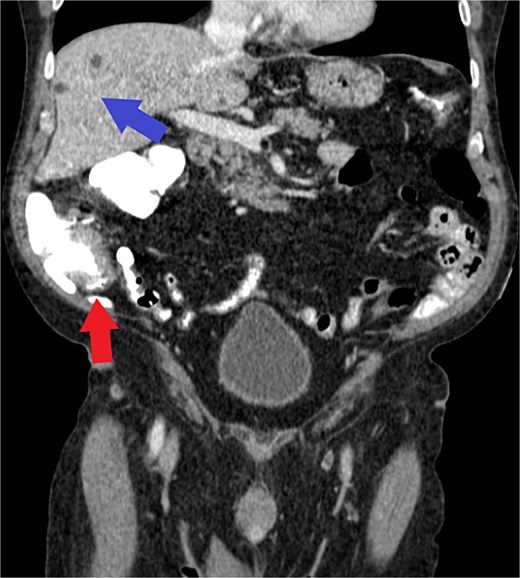

Computed tomography (CT) chest/abdomen/pelvis was ordered for staging. It showed focal wall thickening of the medial cecum, a 2.2 × 1.8 cm mesenteric lymph node in the right lower quadrant, and no evidence of metastatic liver disease (Fig. 2). A CT abdomen/pelvis from the previous year was used for comparison, showing multiple hepatic cysts, an enlarged prostate, and a left renal cyst, but an otherwise normal spleen, pancreas, bowel, and lymph nodes. Colorectal surgery was consulted, and the patient underwent a laparotomy and right hemicolectomy along oncological principles for a multifocal, poorly differentiated adenocarcinoma with mucinous, signet ring cell, and sarcomatoid features.

Axial view of CT demonstrating cecal wall thickening (red arrow) and benign hepatic cysts (blue arrow) without evidence of metastatic disease. Note: Histologic or gross specimen images are not available for this case.